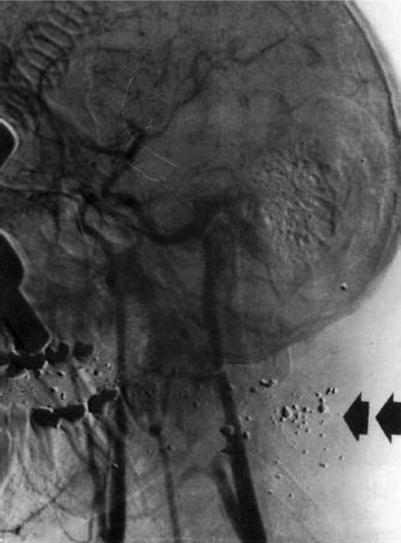

Fig. 33.3

CTA has replaced angiography as the initial study of choice in the vascular evaluation of a neck injury (here in patient with fragmented gunshot neck) Arrows indicate bullet fragments and injury tract with external carotid injury